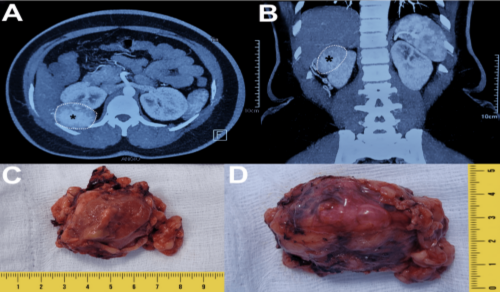

Vinay Nagendra Kaushik, Gopalkrishna Sp, Srikanth Kulkarni

Malakoplakia, derived from the Greek term for "soft

plaque", [] is a rare chronic inflammatory disease first

identified by Professor von Hansemann in 1901 and reported

by Michaelis and Guttman in 1902. Although benign, it

frequently resembles malignant carcinomas due to its tumorlike

mass formations, complicating its diagnosis. Depending

on the location, the disease typically manifests as raised, grey

lesions of varying sizes or soft, yellow mucosal plaques during

physical examination [].

Though malakoplakia can affect multiple organs, it

primarily targets the urinary system, especially the bladder,

with less frequent involvement of the kidneys and ureters [].

Malakoplakia in the urinary system can lead to acute kidney

injury, frequent urinary tract infections (UTIs), and renal

failure, but is rarely fatal [].

The symptoms vary depending on the affected organ: in

cases involving the urinary tract and/or bladder, patients may

experience frequent urination, urinary urgency accompanied

by vague discomfort, hematuria, and bladder irritability; in

instances of renal and ureteral involvement, symptoms can

include lower back pain and fever [,].

The exact cause of bladder malakoplakia is poorly understood,

but its pathogenesis is based on three primary hypotheses. The

first hypothesis suggests bacterial infections, particularly those

caused by E. coli, often occuring after a prolonged and recurrent

history of chronic UTIs. The bladder's local environment

fosters bacterial proliferation and triggers an inflammatory

reaction in the bladder lining []. The second hypothesis points

to immunocompromised states or long-term chronic conditions

such as HIV, tuberculosis, sarcoma, diabetes, lymphoma, and

ulcerative colitis []. Third, it is believed to stem from an acquired

defect in the bactericidal function of macrophages. Normal

microtubular function and phagolysosomal activity require betaglucuronidase

and cyclic guanosine monophosphate (cGMP).

Reduced levels of these enzymes result in impaired clearance of

pathogenic organisms due to the persistence of phagolysosomes.

The characteristic Michaelis-Gutman bodies, which are calcified

intracytoplasmic inclusions, represent the phagolysosomes that

have failed to undergo exocytosis [,,].

Malakoplakia in the genitourinary system typically shows

a higher prevalence in females, with a female-to-male ratio

of 4:1. The age of diagnosis can range from six weeks to 85

years, with the average age at which individuals start showing

symptoms being 50 years [,].